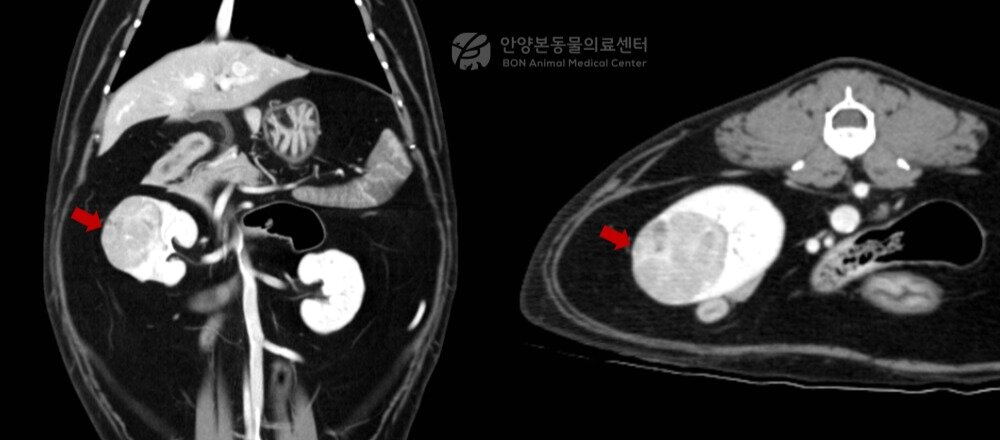

본문 이미지 - 수술 전 정밀 평가를 위한 신장 CT 검사 결과 2.2x2.2x3.0㎝ 크기 종괴가 확인됐다(병원 제공). ⓒ 뉴스1

수술 전 정밀 평가를 위한 신장 CT 검사 결과 2.2x2.2x3.0㎝ 크기 종괴가 확인됐다(병원 제공). ⓒ 뉴스1